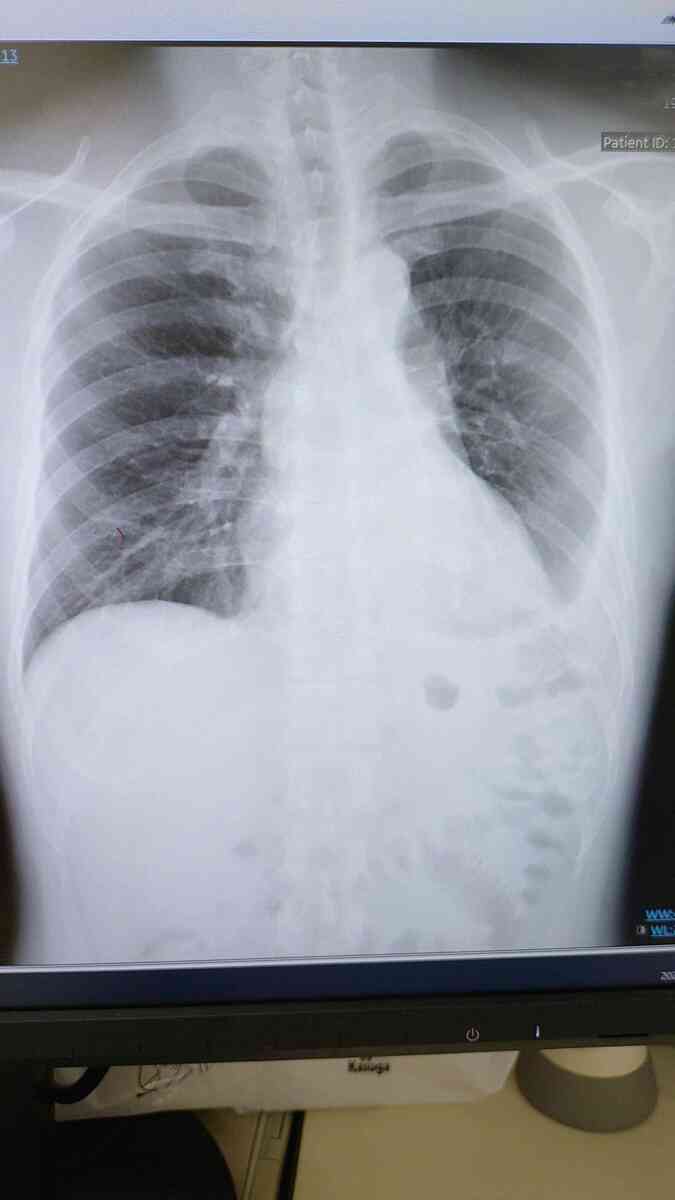

まずはコチラ、上は退院時で下は今日のワタシの肺です😀

上は左肺(写真では右側)の下に水が溜まっていて、右肺もやや萎んでいます。

下は左肺の水が無くなって右肺も大きくなっています☺️回復は時間がかかりましたが、軌道に乗って来ました